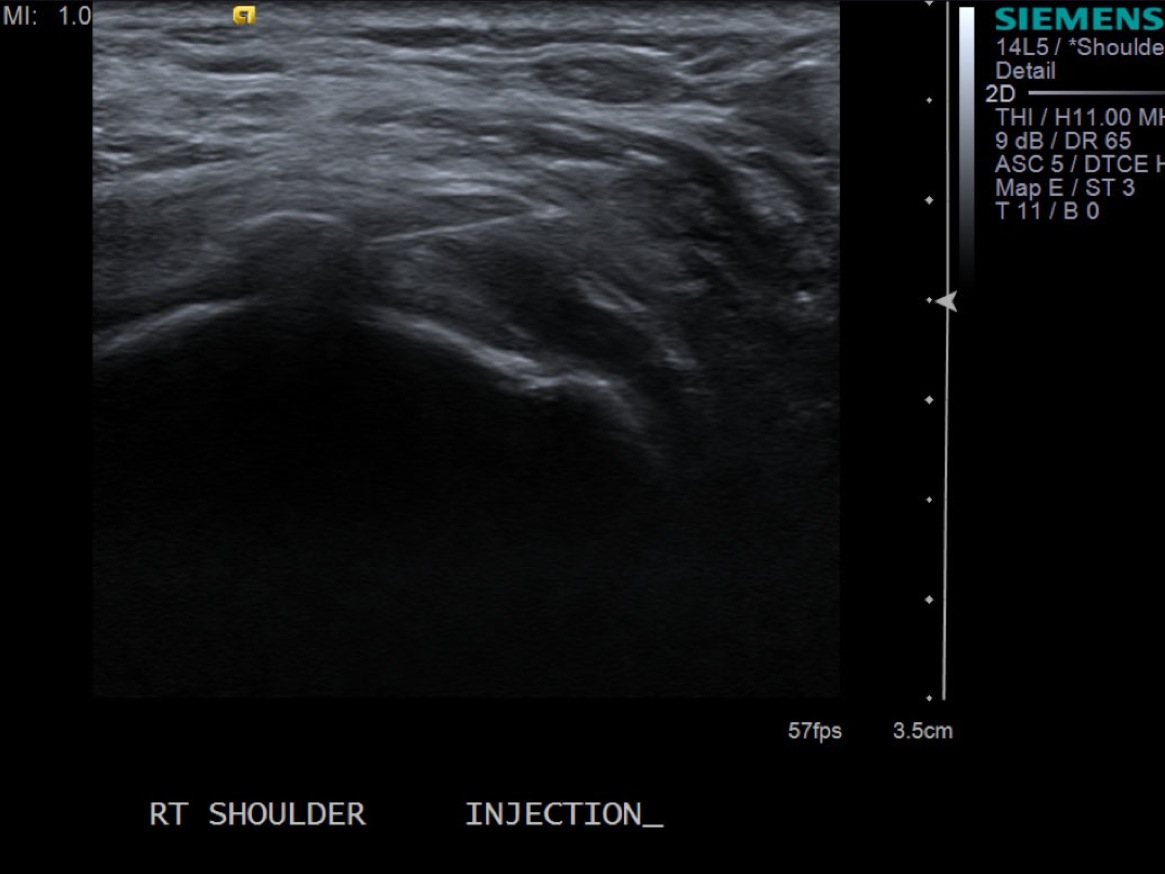

• descriptiondescription

Short axis view of supraspinatus tendon with calcific deposit